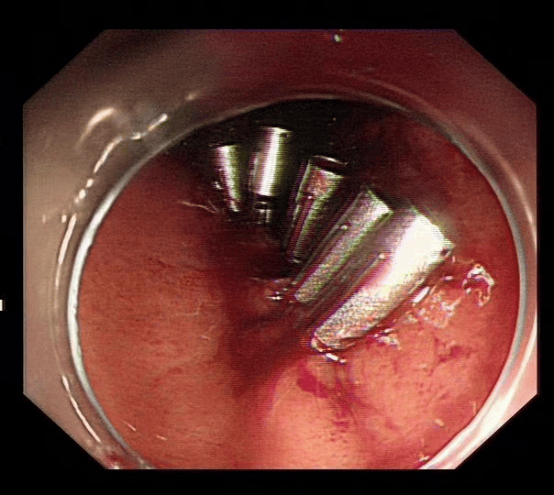

患者在胃镜检查时发现胃粘膜下肿物,考虑间质瘤可能,如不及时切除有可能恶变,需行内镜下粘膜剥离术(ESD)。由于此手术创伤小、恢复快,经与患者及家属沟通后,完善相关术前准备后,在安徽省第二人民医院消化内科王俊先主任指导下,消化内科、内镜中心及麻醉科医护人员的密切配合下,成功为患者进行手术,术中无明显出血、穿孔,术后各项生理指标正常,手术取得圆满成功。

ESD即内镜粘膜下剥离术,方法是在内镜粘膜下注射基础上利用几种特殊的高频电刀,将病变所在粘膜剥离。通过ESD可完整的切除病变,达到根治消化道肿瘤的效果。